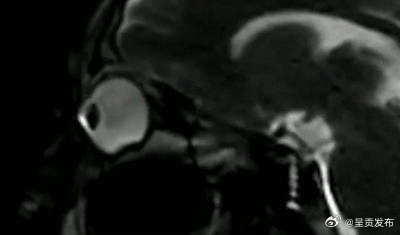

飞进眼里的脏东西最后都去哪了眼睛里进东西时,很多人下意识会揉揉眼睛,揉眼睛不仅会伤到眼球,还会使眼皮随着时间的推移而失去弹性。如果手指不小心碰到角膜,或将眼睛里的异物揉入结膜囊,可能导致角膜上皮损伤。角膜上皮损伤后虽然可以修复,但缺少角膜上皮保护的角膜容易遭受病菌的侵犯。在核磁共振影像下,揉眼睛时的眼球变化是这样的↓↓(@生命时报)